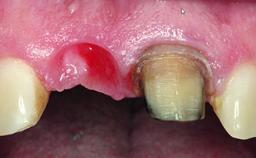

Placement Protocol Immediate implant placement

Socket Integrity Damage to one or more bone walls

Bone Volume Damage to one or more socket walls